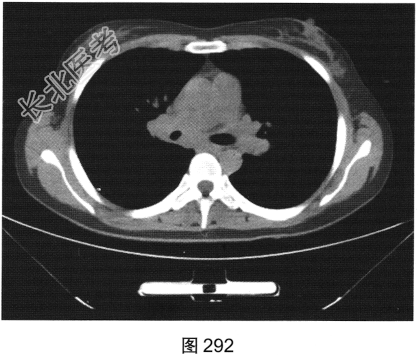

- [材料题] 患者女性,43岁,因“确诊肺低分化腺癌1周”就诊。患者于2014年11月无明显诱因出现咳嗽、咳痰,无胸闷胸痛,无咯血,无发热、乏力、体重减轻等。自服中药治疗,止咳效果尚可。2015年4月22日在山海关人民医院行胸部CT:显示①慢性支气管炎继发感染,建议结合临床及病史考虑;②右侧中间段支气管及中叶支气管壁增厚、管腔狭窄伴右肺中叶阻塞性肺不张,右侧肺门及纵隔多发淋巴结增大,建议增强扫描。后补做增强CT:右肺中叶支气管增厚,管腔狭窄伴阻塞性肺不张,考虑右侧中心型肺癌伴纵隔多发淋巴结增大,建议行支气管镜检查。支气管镜取活检病理:示低分化腺(右肺中叶)癌,建议做免疫组织化学检测,以进一步明确诊断。于北京肿瘤医院行PET/CT检查:①右肺中叶支气管起始部位高代谢结节,符合中心型肺癌表现;右肺中叶部位阻塞性不张,不张肺内高代谢结节,倾向肺内转移;双肺多发转移结节;双锁骨上区、左胸肌间、纵隔及双肺门多发淋巴结转移。②脑部未见明显高代谢征象,建议行增强MRI检查。③双叶甲状腺炎性或非特异性摄取,建议行B超及甲状腺功能检查。患者精神状态良好,体力、食欲、睡眠均正常,体重无明显变化,大便、排尿正常,为进一步检查及治疗,门诊以“肺癌”收入院。2015年5月5日在我院行CT检查,如图288~图295所示。